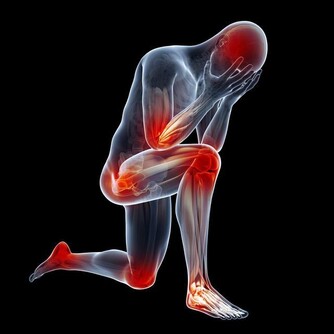

當人體遇冷時,血管收縮,血流速度減慢,血液中輸送的人體所需的各種養料和氧氣就會減少,而膝關節支撐人的身體,本身周圍血管少,血流速度就差,若穿著短褲、短裙則會使膝關節暴露在低溫環境,膝關節長時間受寒涼刺激,血液循環更慢,更易出現水腫和炎症改變,導致滑囊炎、滑膜炎等關節性疾病。